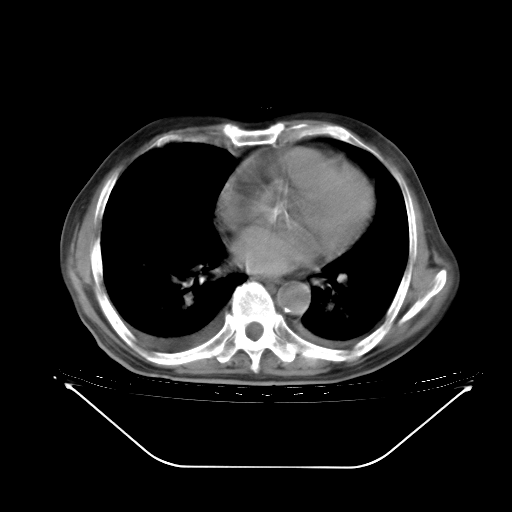

今天复查肺部CT,发现双肺广泛磨玻璃样改变。所以我把3月19日和5月9日相隔50天的肺部CT上传。请大家会诊。

2009年3月19日肺部CT片。

5月9日肺部CT(在4月27日齐鲁医院肺部CT描述部分肺组织磨玻璃样改变,12天后肺组织广泛磨玻璃样改变)